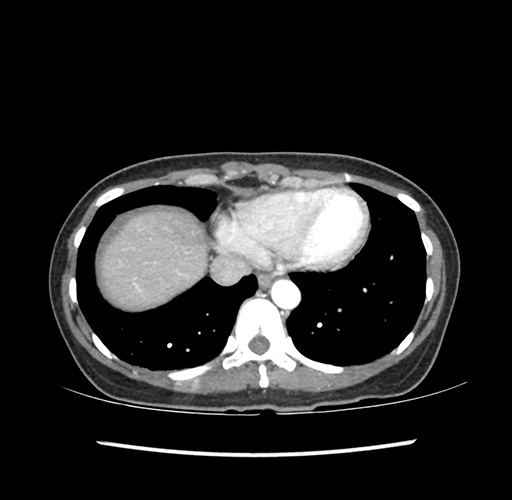

Imaging Analysis

Look through the patient's CT scan to identify any areas of concern for the necessary procedure.

Based on your CT findings, which issue(s) would give reason for "planned slowing down moment(s)" in this case?

Considering a standard left lateral sectionectomy procedure, what step(s) of the operation would you do differently in this case ?